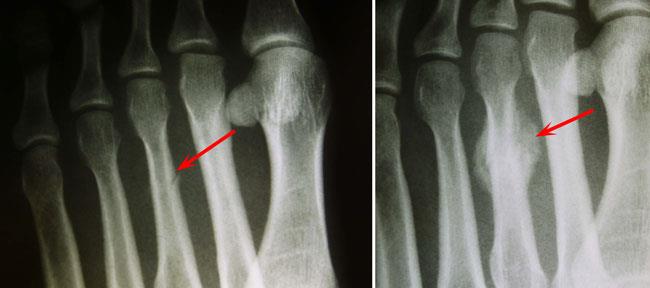

One or more of these bones may be fractured after an injury to t. Toe Fracture Uva Health

However, the bones of the foot are understandably stronger and capable of carrying more weight, a feature that comes at the cost of mobility. So you've got a deformity in your toe where it bends or points downward and causes pain and discomfort? To be, or not to be: Each toe is made up of several bones. Broken toes are common injuries. Hammer toe is a common toe deformity that occurs due to imbalance in the surrounding muscles. The feet and hands have similar skeletal structures. Webmd explains the causes, symptoms, diagnosis, treatment, and outlook for a broken toe.